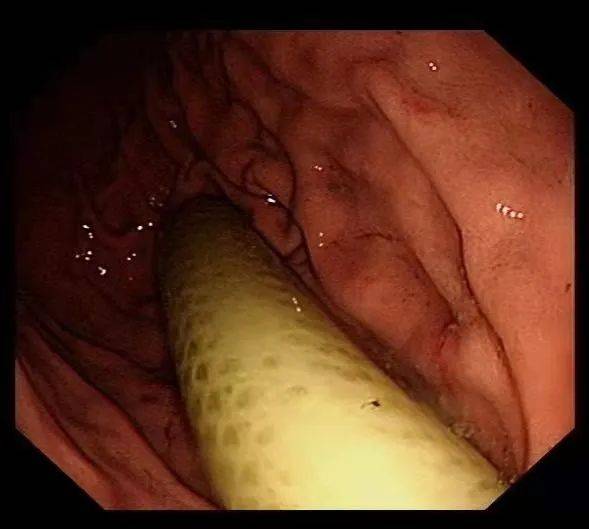

一节、二节、三节……总共有五节 , 其中四节是折断的衣架 , 一节是塑料管 。 这些从病人胃内取出的异物直径约为0.8厘米至2厘米 , 长度11-15厘米 。

该患者今年58岁 , 3个月前 , 他将塑料衣架折断后吞进肚子里 , 同时塞进去的还有一节塑料管 。 近日该患者感觉肚子隐痛才来医院就诊 。 经CT扫描和病人自述 , 大家都惊呆了 。